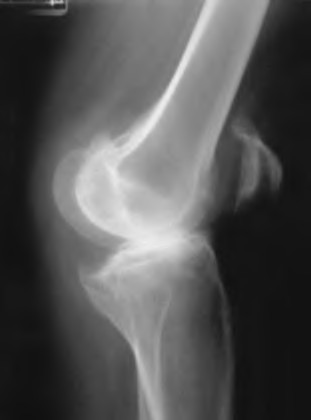

Question 37

A 35-year-old male presents with right hip pain. MRI confirms avascular necrosis (AVN) of the femoral head. Radiographs show a distinct sclerotic band and cystic changes in the femoral head, but no subchondral collapse or crescent sign. According to the Ficat and Arlet classification, what stage is this, and is core decompression generally indicated?